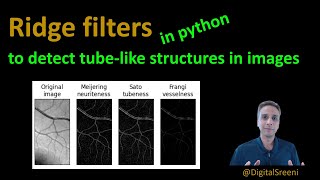

Plot Ridge Filter || meijering, sato, frangi, hessian || Citra Digital video

Plot Ridge Filter || meijering, sato, frangi, hessian || Citra Digital

Plot Ridge Filter || meijering, sato, frangi, hessian || Citra Digital Kixcodes Explains Image processing - Frangi filter

Kixcodes Explains Image processing - Frangi filter 104 - Ridge Filters to detect tube like structures in images

104 - Ridge Filters to detect tube like structures in images 125 frangi

Plot Ridge Filter || meijering, sato, frangi, hessian || Citra Digital

Plot Ridge Filter || meijering, sato, frangi, hessian || Citra Digital Kixcodes Explains Image processing - Frangi filter

Kixcodes Explains Image processing - Frangi filter 104 - Ridge Filters to detect tube like structures in images

104 - Ridge Filters to detect tube like structures in images 125 frangi